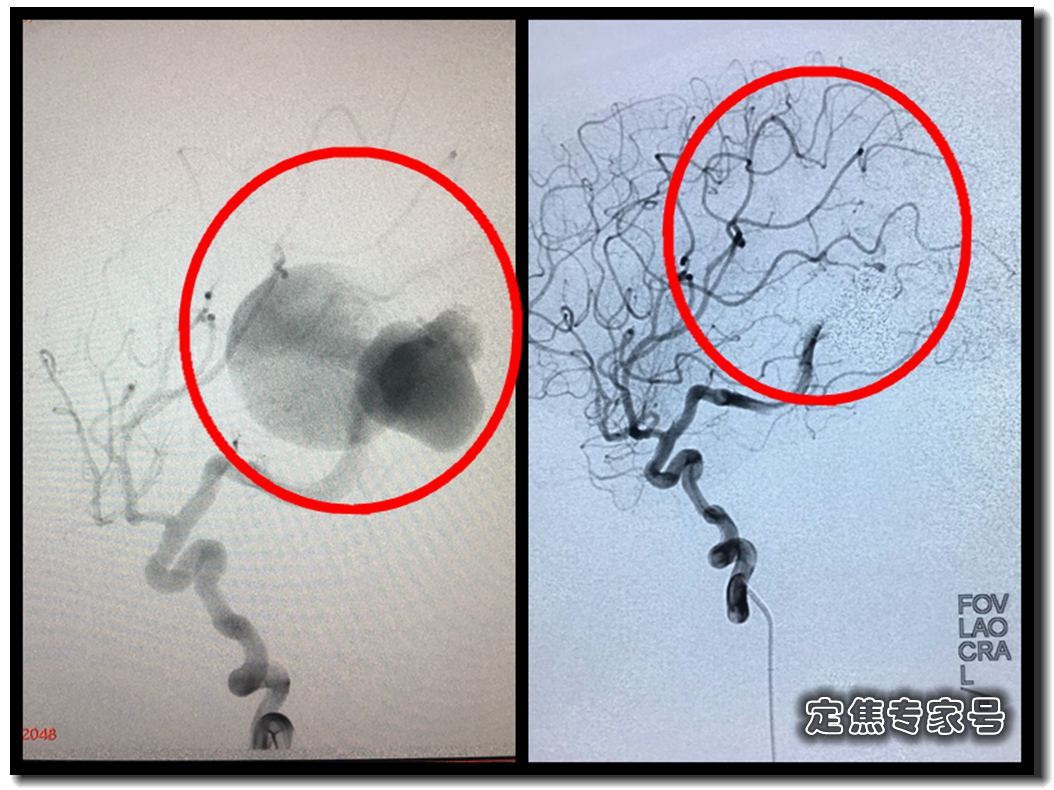

5月22日,北京天坛普华医院主任医师,副教授卢旺盛和北京天坛医院知名专家共同为小飞紧急做了介入手术,也就是通过小飞大腿根的动脉,把细细的导管一直插到大脑这个瘤子里,在瘤子里塞入弹簧圈,有点类似我们刷碗的那种钢丝球,同时注入在血液中凝固的胶,填满其间空隙,像钢筋混凝土,同时也把动脉和静脉之间那个洞堵上。被血液吹大的“气球”被弹簧圈填满的同时,还断了血液供应,自然就萎缩了。

这是手术前后的造影图。可以看出来,术前血液都跑到两个大球里,大脑供血几乎看不到。而术后,大黑球消失,瘤子所处的大脑区域有了明显的血液供应,枝杈丰富,几乎能听见血液在此前干瘪的血管中欢快地奔腾。